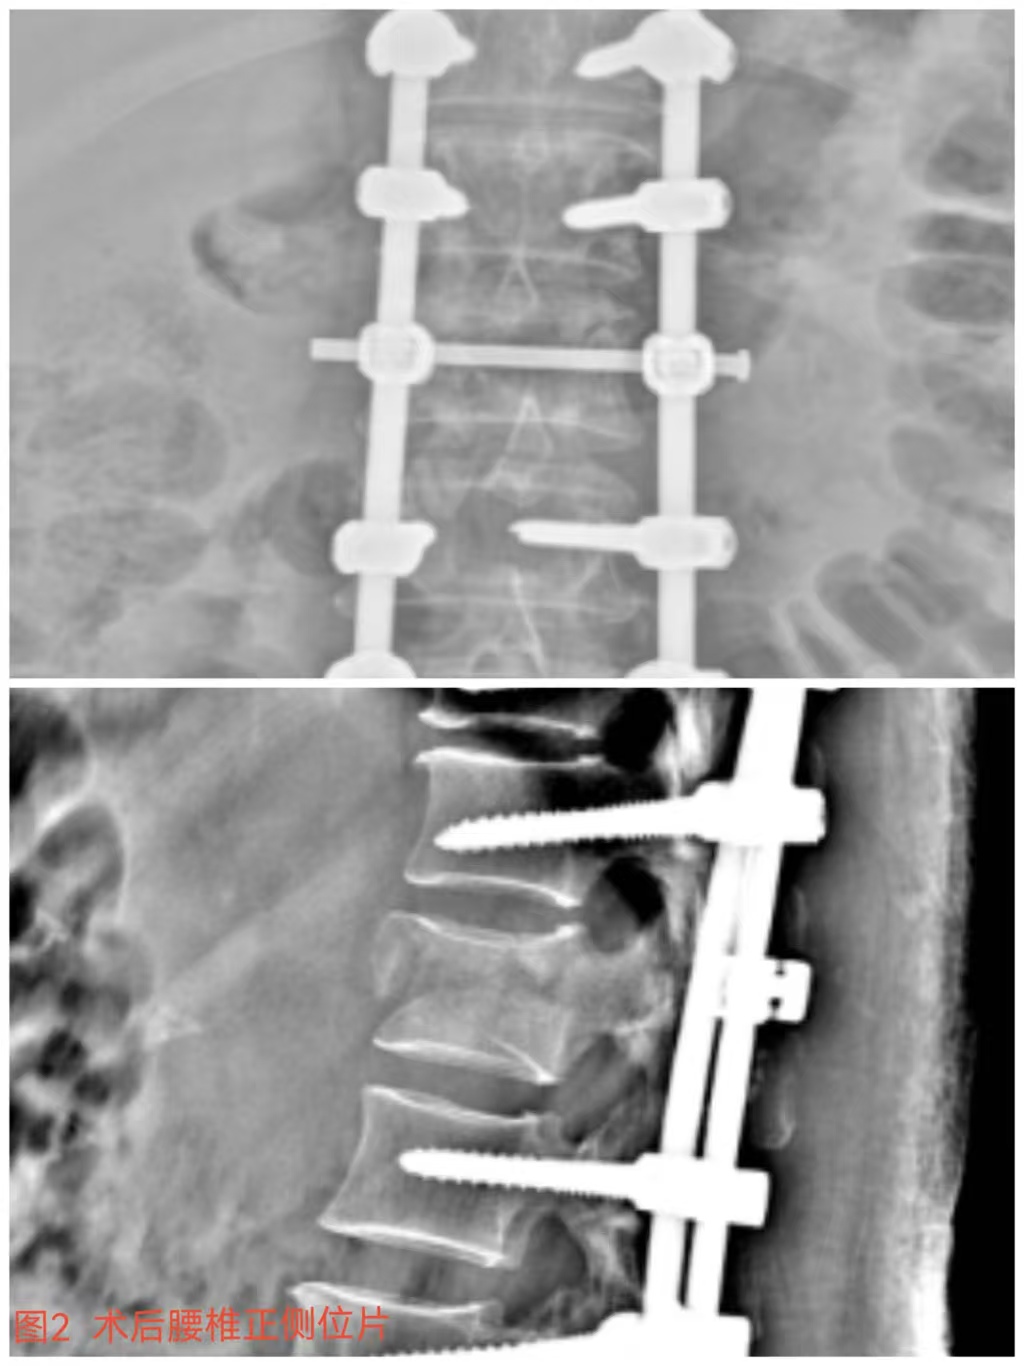

俞德亮副主任醫師深知病情的嚴重性,拖得時間越久,脊髓神經損傷癥狀越難以恢復,必須把握住早期減壓手術的關鍵時間窗,緊急帶領創傷骨科醫師團隊對該病情進行討論、制定手術方案,并成功為患者急診行“L1椎體爆裂性骨折伴截癱切開椎板切除+椎管探查減壓+骨折復位釘棒系統內固定術(圖2)”,該手術精確解除對脊髓神經的壓迫,并通過椎弓根螺釘內固定系統對受損的腰椎提供穩固的支撐,為后期的康復創造了良好的條件。